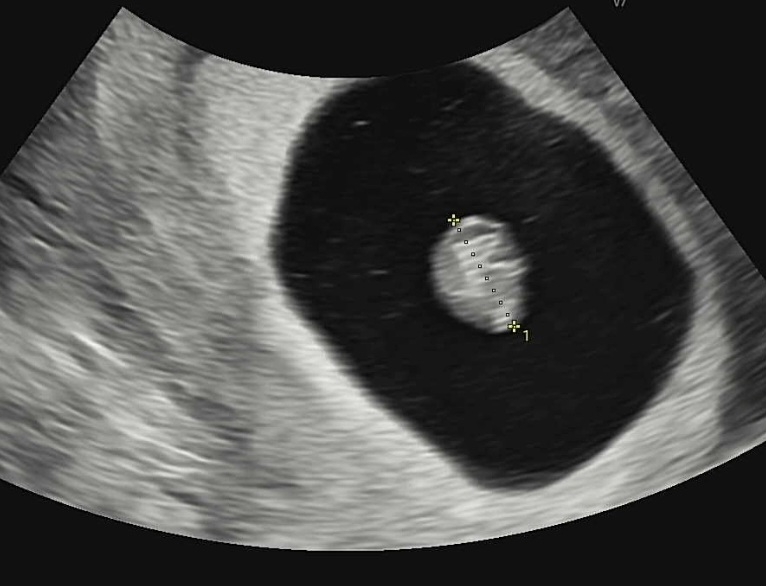

오늘 심장소리 듣고왔어요!!ㅎㅎ 애기가 엄청 커있어요 강낭콩같이 너무 귀엽더라구요 너무 감격스럽습니다ㅠㅠㅠ 얼마나 크려는지 입덧도 심해져서 입덧약도 처방해왔어요

지난 주(6주2일)에 방문했을 때 아기집만 보였어요. 오늘 방문(7주2일)하니 난황에 아기, 심장까지 잘 보이더리구요! 걱정마세요!